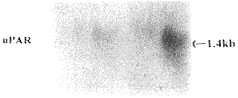

2.2 Norther印迹杂交结果 提取的组织总RNA,运用uPA、uPARcDMA探针进行cDNA-mRNANorthern印迹杂交,并采用β-actin探针作为内标校正加样量的误差。依据公式计算胃癌和癌旁组织中uPA和uPARmRNA表达差异。结果显示,在20例胃癌组织中,有13例(占65.0%)uPARmRNA表达高于癌旁组织,平均高4.2倍。15例(占75.0%)uPARmRNA表达高于癌旁组织,平均高5.6倍(图2);出现uPA、uPARmRNA高表达的胃癌组织中有12例二者协同高表达,其中11例伴有淋巴结转移。在这11例伴有淋巴结转移的胃癌组织中,uPA和uPARmRNA表达水平均显著高于9例无淋巴结转移者,其中uPA平均高4.7倍(P<0.05),uPAR平均高6.3倍(P<0.01)。

图2 uPA和uPARmRNANorthern杂交

T.胃癌组织;N.相应癌旁组织

本研究通过Northern印迹杂交方法检测20例胃癌和相应癌旁组织中uPA和uPARmRNA表达水平。结果,胃癌和癌旁组织均出现单一转录带,转录带长度分别为2.5kb和1.4kb,符合文献报道的uPA和uPARmRNA分子量大小,表明该杂交检出的uPA和uPARmRNA是特异的。